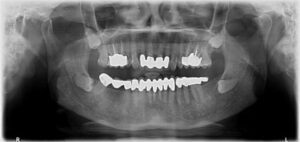

Wisdom teeth, or third molars, are the last teeth to develop and appear in your mouth.

They come in between the ages of 17 and 25. When a tooth is unable to fully enter the mouth, it is said to be “impacted.” In general, impacted teeth are unable to break through the gums because there is not enough room. Nine out of ten people have at least one impacted wisdom tooth.